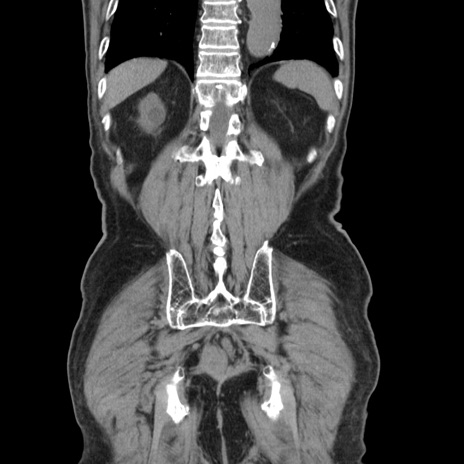

症例24(冠状断像)

【症例】80歳代男性

【主訴】左側腹部痛、嘔吐

【現病歴】本日早朝より左腹部に痛みあり。昼頃嘔吐認めたため、救急要請。

【既往歴】直腸癌(Mile手術)、胆摘

【身体所見】意識清明、BT 35.9℃、BP 221/93mmHg、SpO2 97%(RA) 、腹部:左ストーマ周囲に限局性の腹部膨隆あり。 膨隆部自発痛・圧痛あり・軟。

【データ】WBC 7700、CRP 0.09